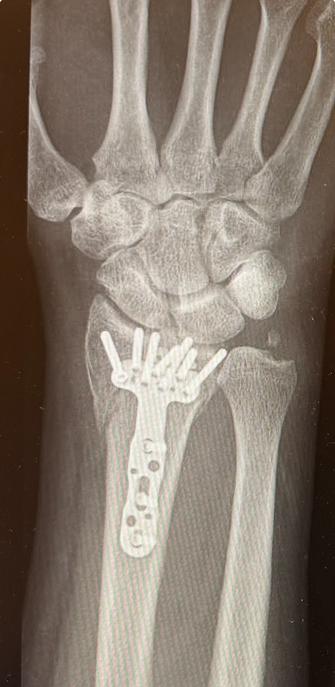

How surgeons fix a broken wrist